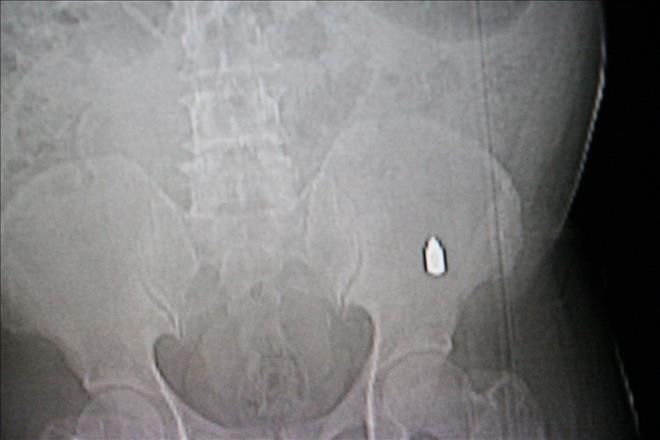

Nusaybin Kışla Mahallesi cumhuriyet ilköğretim okulu mevkide ki boş arsa yanında yürüyen Mehmet Salih Sarohan(51).´´in tespihi yere düşünce eğilip aldığı sırada nerden geldiği belirlenmeyen tabanca kurşunu beline saplandı. Sarohan, çocuklar belki taş atı diye ondan belim acıyor, tahmininde bulundu. Hemen olay yerinde yakınlarına anlatı. Yakınları da Sarohan´ın beline baktı ki bir yara izidir. Yaralı Sarohan yakınları tarafından Nusaybin devlet hastanesi acil servisine kaldırıldı. Burada tedavi altına alındı. Sarohan´ın Rongen filmi çekilince belinde tabanca kurşunu gibi bir cisim belirlendi. Cisim Sarohan´ın belindeki et içine saplanmış gibi gözüktüğü öğrenildi. Sarohan hastaneye yatırılarak kontrol altına alındı. Olayla ilgili polis ekipleri soruşturma başlattı.-Haber-Ahmet Akkuş